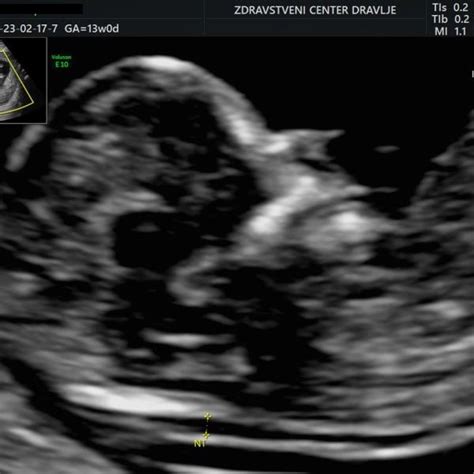

- Priprava: Zdravnik z ultrazvokom natančno določi lego ploda in posteljice ter oceni gestacijsko starost. Pomembno je, da se med ultrazvočnim presejalnim testom NS (nuhalne svetline) določi primerna lega posteljice za BHR. Če je lega posteljice specifična, BHR morda ni vedno možno izvesti dovolj varno, zato se v približno 20 % do 25 % primerov raje odločijo za amniocentezo (AC).

- Transcervikalni postopek: Skozi maternični vrat se vstavi tanek kateter. Ta pristop se lahko uporabi, če je posteljica zadaj in ni dostopna skozi trebuh, vendar je lahko tehnično zahtevnejši.Med celotnim postopkom zdravnik ves čas spremlja potek s pomočjo ultrazvoka, da zagotovi varnost nosečnice in ploda. Pogosto se mesto vboda predhodno infiltrira z lokalnim anestetikom, da se zmanjša bolečina. Sam postopek običajno traja le nekaj minut.